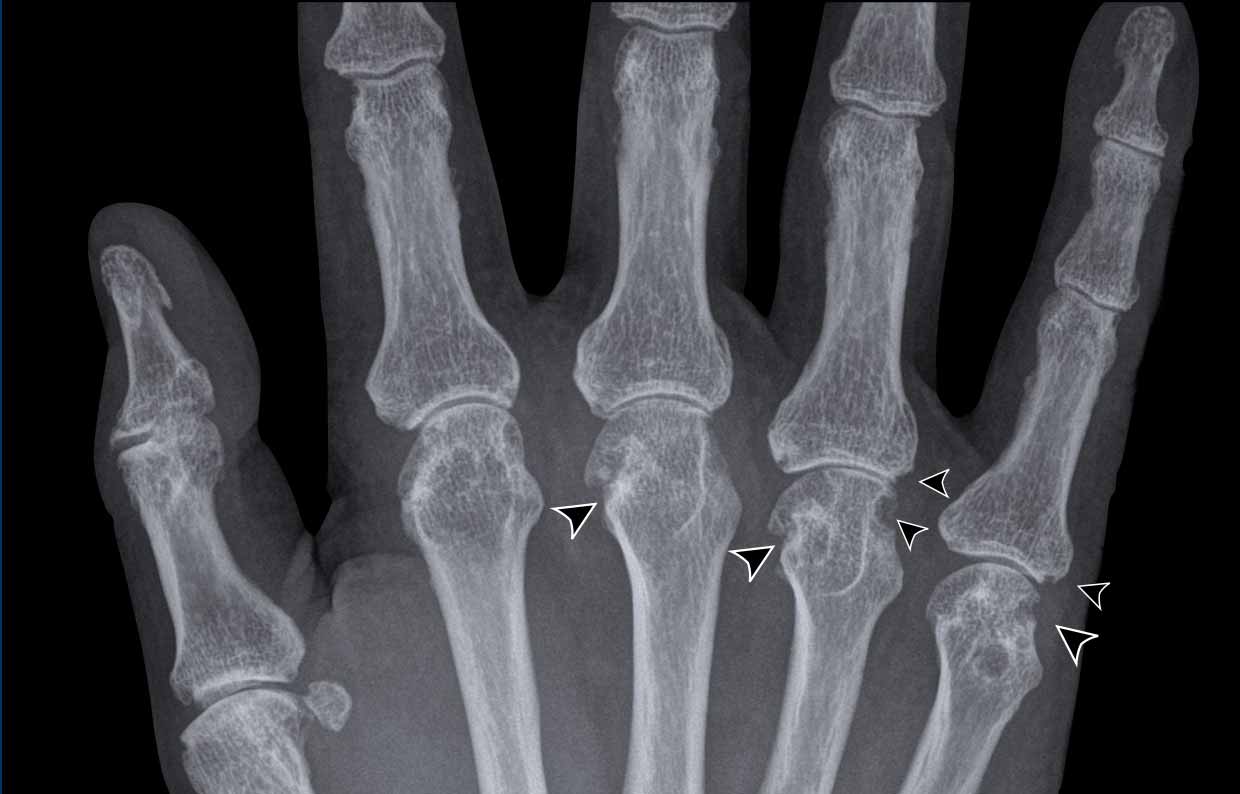

Dip Joint Space Narrowing . Mild osteoarthritis (oa) causes joint pain and stiffness. If osteoarthritis is suspected, radiographs should be taken of the most symptomatic joints. Osteophytes and joint space narrowing affecting a few of the distal interphalangeal joint (dipj), mainly the third fingers. A condition such as arthritis will cause the space to narrow. A doctor can use this to assess the. The distal interphalangeal (dip) joint connects the bones at the tips of the fingers. Diagnosis is made radiographically with joint. People with arthritis may experience pain, stiffness, and swelling in this joint. Radiographs generally reveal marginal osteophytes, narrowing of the joint space, increased density. Arthritis of the dip and pip joints are very common forms of osteoarthritis seen in the hand and can be associated with pain and deformity. Joint space narrowing (jsn) refers to the space between the bones in a person's joints. The joint space narrowing, a core feature of eoa and psa, is strictly related to loss of articular function;

Dip Joint Space Narrowing Osteophytes and joint space narrowing affecting a few of the distal interphalangeal joint (dipj), mainly the third fingers. If osteoarthritis is suspected, radiographs should be taken of the most symptomatic joints. Joint space narrowing (jsn) refers to the space between the bones in a person's joints. Osteophytes and joint space narrowing affecting a few of the distal interphalangeal joint (dipj), mainly the third fingers. Radiographs generally reveal marginal osteophytes, narrowing of the joint space, increased density. The joint space narrowing, a core feature of eoa and psa, is strictly related to loss of articular function; The distal interphalangeal (dip) joint connects the bones at the tips of the fingers. People with arthritis may experience pain, stiffness, and swelling in this joint. Mild osteoarthritis (oa) causes joint pain and stiffness. A condition such as arthritis will cause the space to narrow. Arthritis of the dip and pip joints are very common forms of osteoarthritis seen in the hand and can be associated with pain and deformity. A doctor can use this to assess the. Diagnosis is made radiographically with joint.